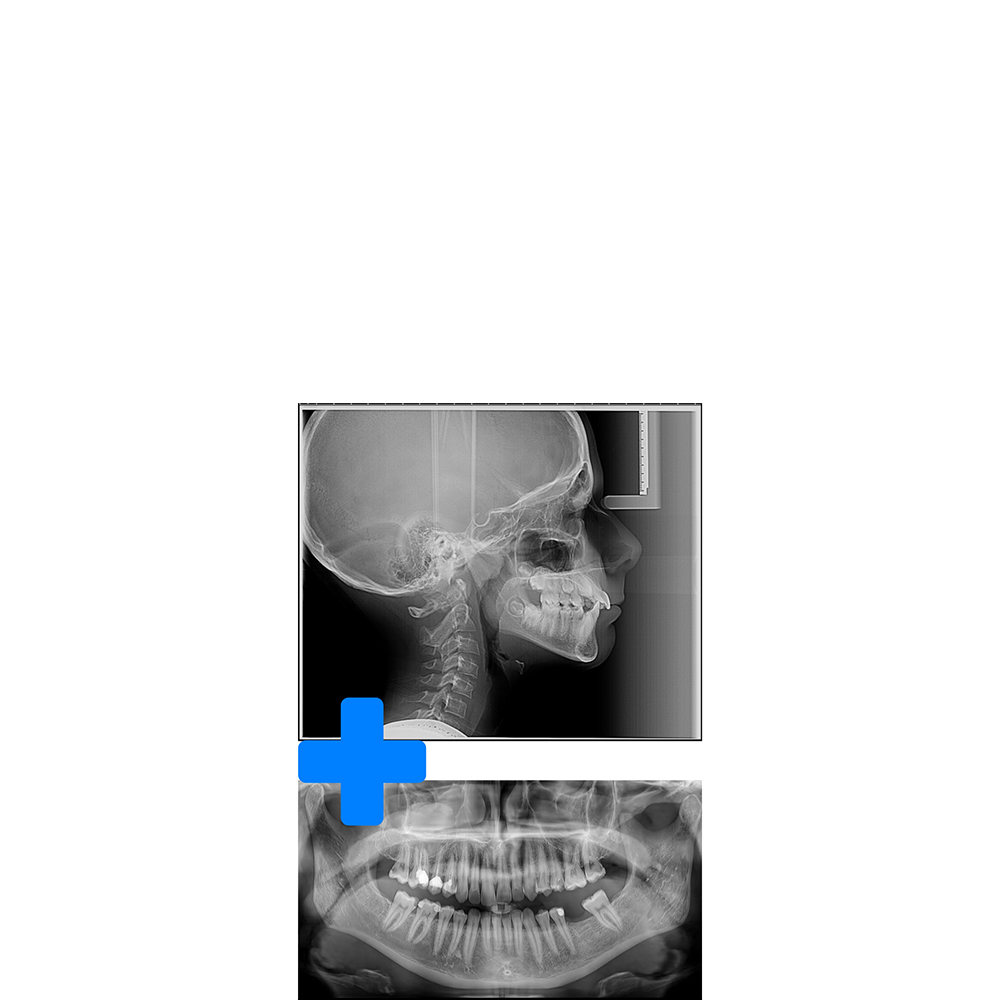

Pachet Orto (OPG+CEPH)

Pachetul ortodontic include radiografia panoramică (OPG) și teleradiografia de profil (CEPH), fiind setul standard de investigații necesar pentru începerea unui tratament ortodontic.

210 RON